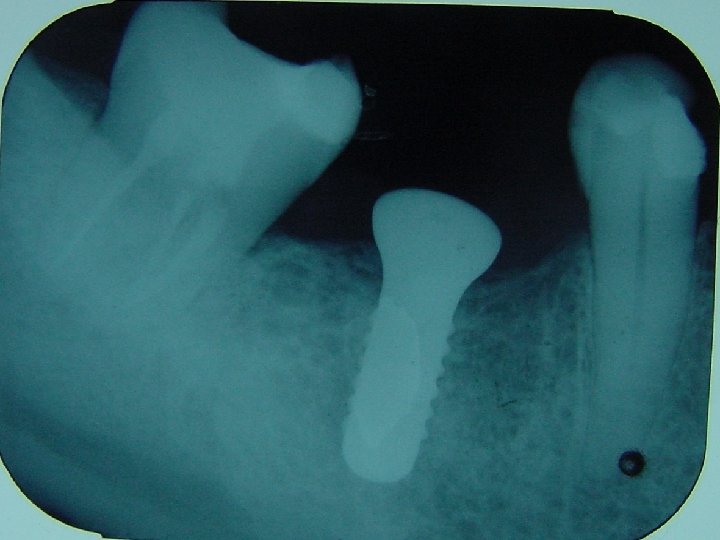

Espaços protéticos com 8 a 10 mm de comprimento poderão ser resolvidos com implante de 3, 75 mm ou 4 mm de diâmetro.

Espaços protéticos maiores deverão receber implante de maior diametro sempre que possível.

Espaços protéticos com 8 a 10 mm de comprimento poderão ser resolvidos com implante de 3, 75 mm ou 4 mm de comprimento. Espaços maiores poderemos lançar mão de dois implantes de diâmetro convencional.

X= 14 -17 mm (2 implantes de diâmetro convencional) X=18 -20 mm (2 implantes de maior diâmetro)